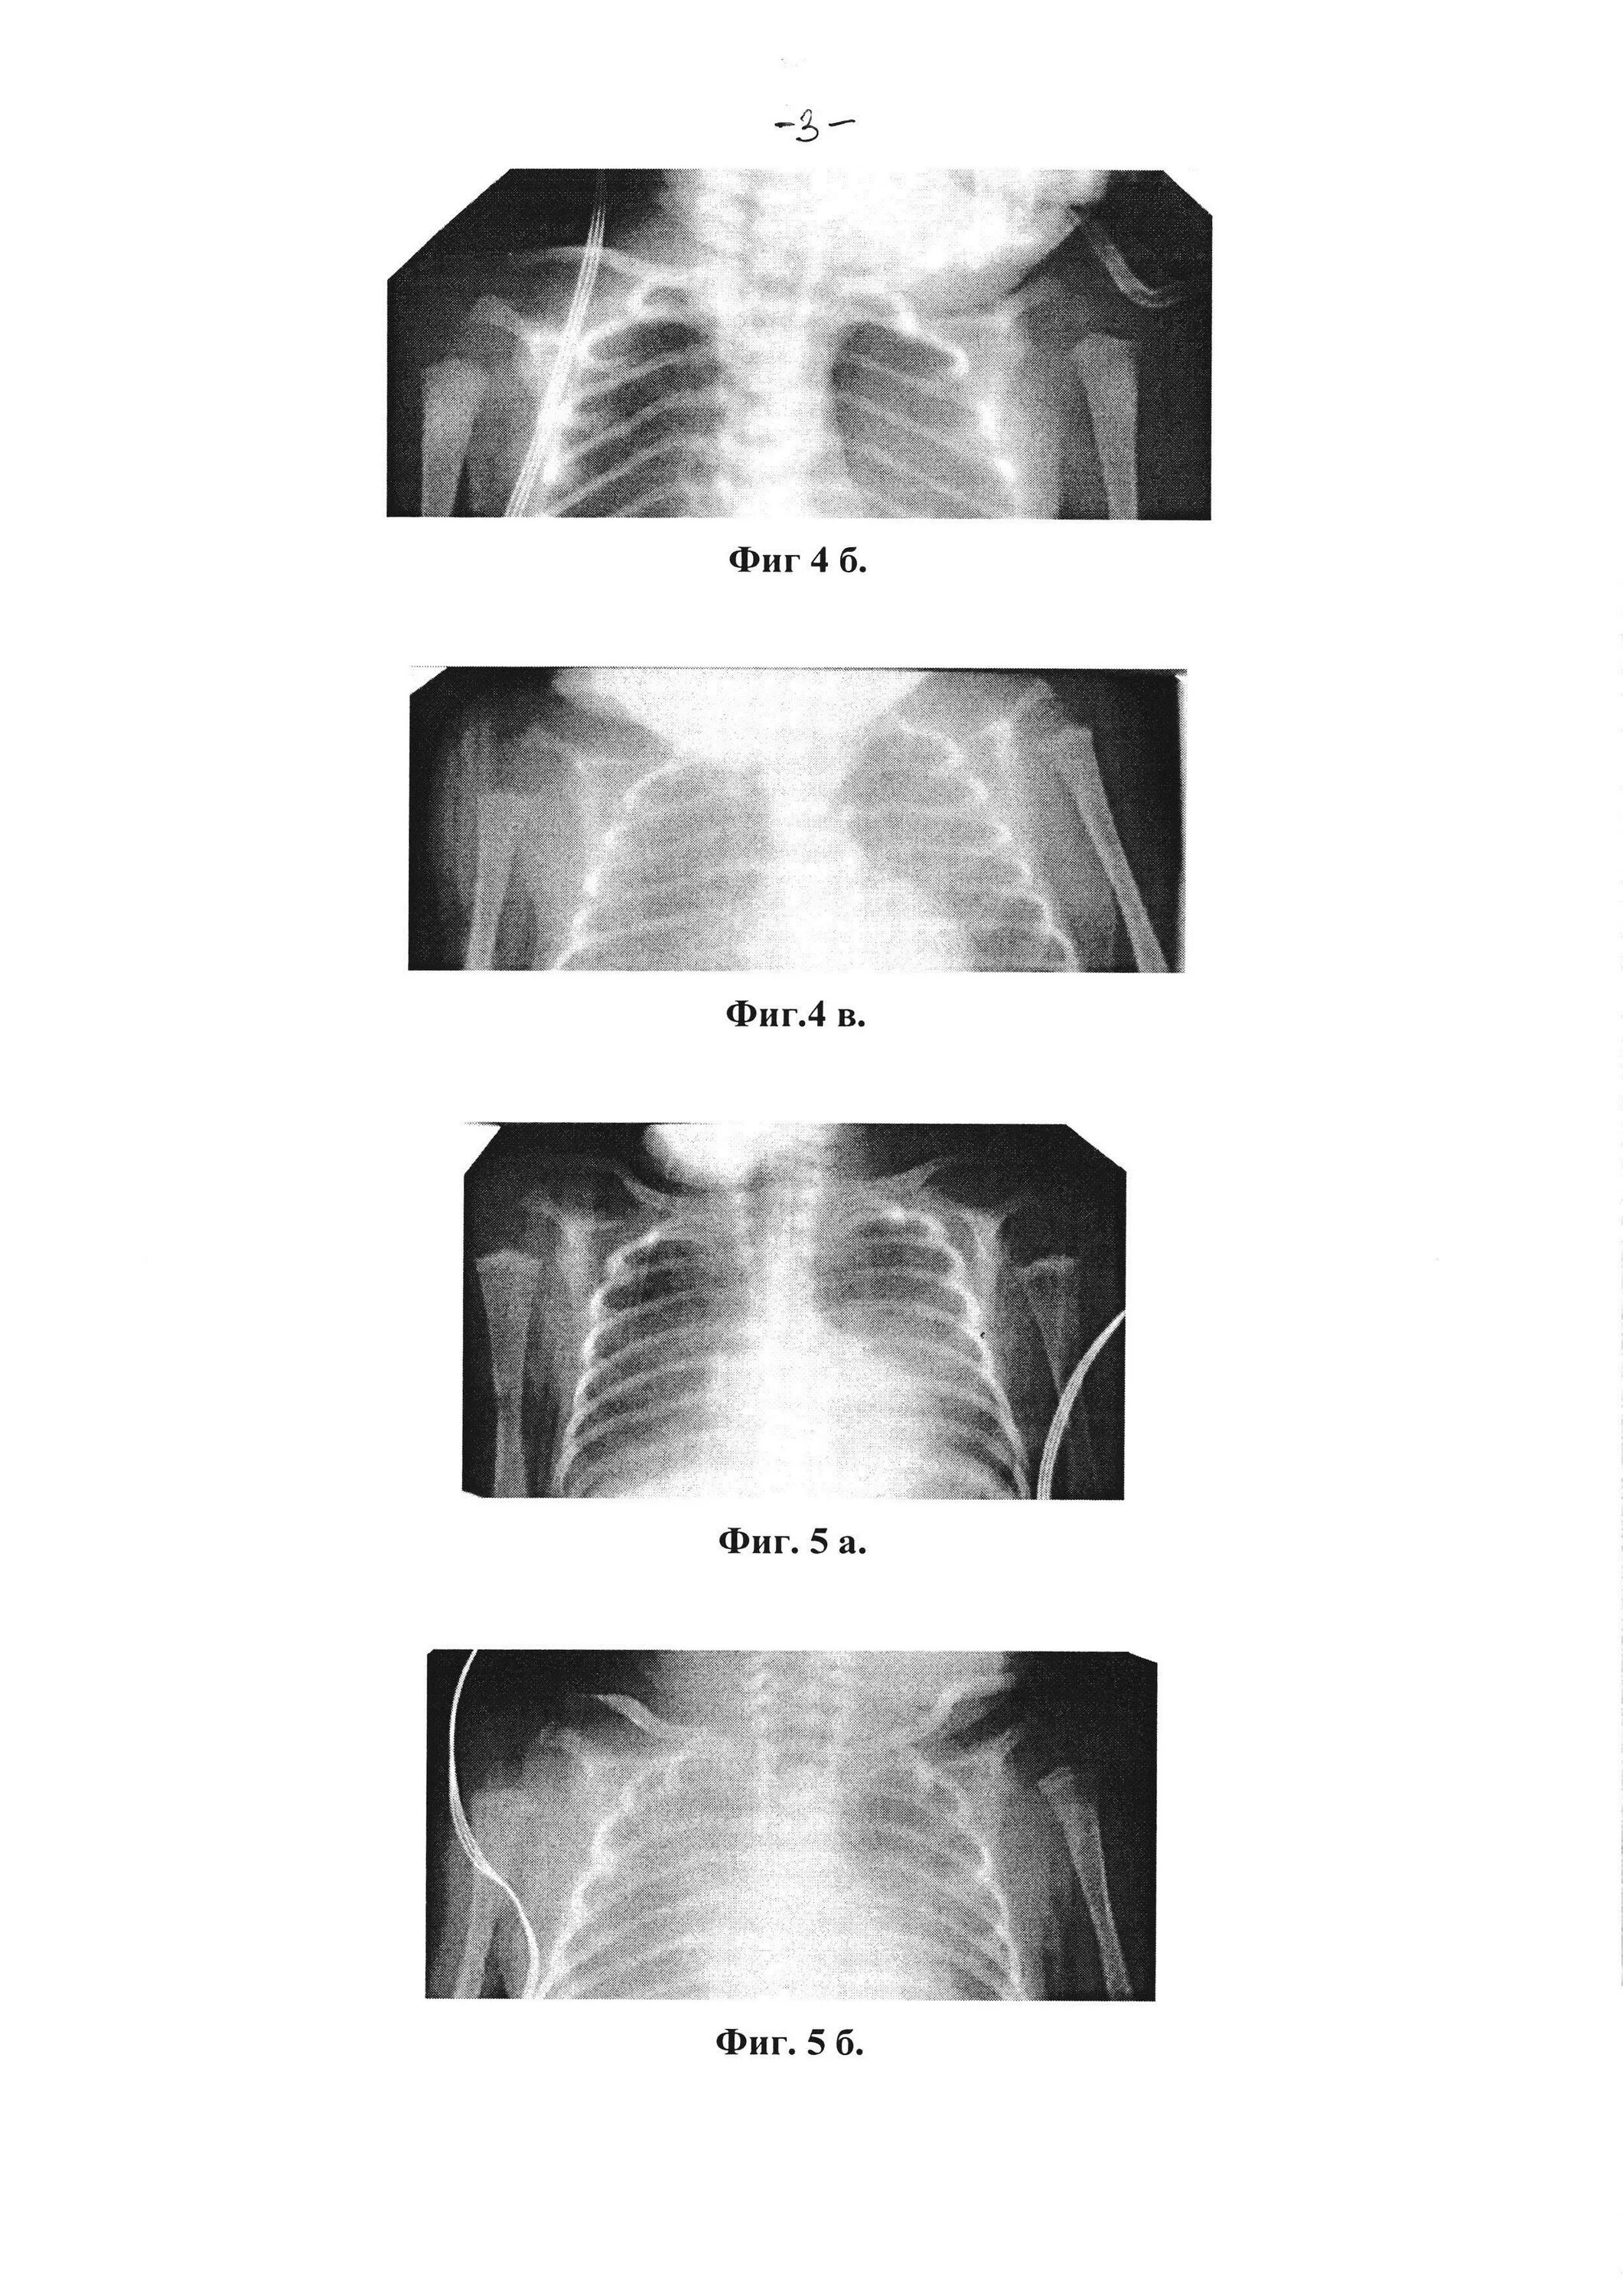

Рахит недоношенных детей